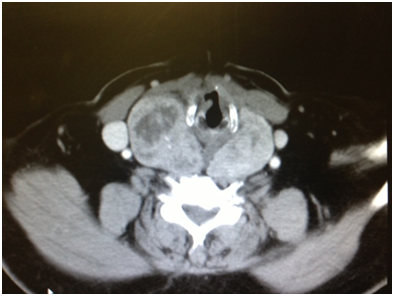

Based on the case report we presented, it is recommended that patients seen with symptoms like those of benign paroxysmal positional vertigo who do not show improvement after undergoing the particle repositioning maneuver should have imaging studies of neck and brain. Measuring artery flow in neutral and neck rotated position using Doppler ultrasonography and comparing the results may be diagnostic in patients with vertigo due to vascular compression. However, the procedure is not practical because it is difficult to scan the distal part of the artery during rotation.3 CT angiography may be considered an alternative option (Figure 1–3).

Figure 2 CT scan soft tissue neck showing right thyroid lobe enlargement at the level of hyoid bone, again displacing carotid artery.